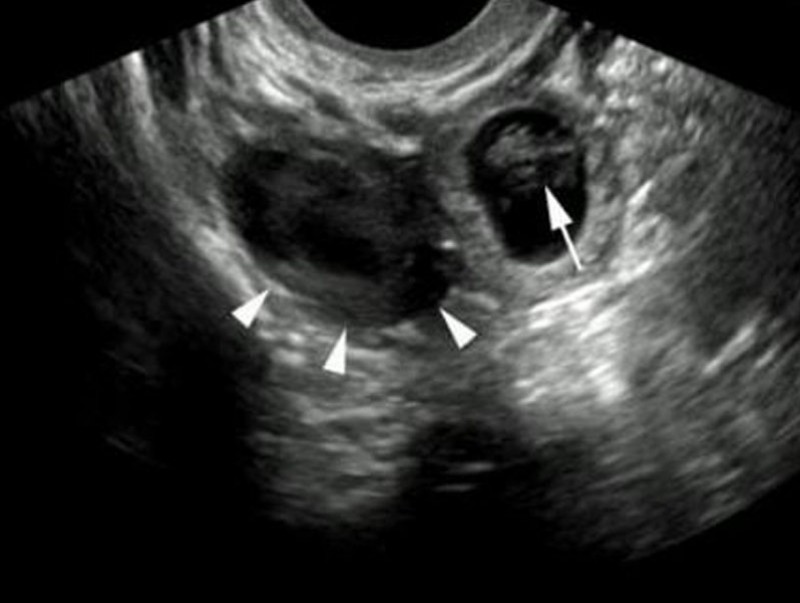

• Хэт авиан шинжилгээ. Хэрэв эмч хэв авиан шинжилгээгээр гуурсан хоолойд байгаа хөврөлийг илрүүлж чадвал умайн гаднах жирэмслэлт гэдэг нь тодорхой болно. Гэвч ихэнх тохиолдолд хөврөл эрт үедээ амьгүй болдог бөгөөд ийм үед хэт авиан шинжилгээнд илрэхгүй байж болдог. Харин үүний оронд гуурсан хоолой хөөж томорсон, хөврөлөөс үлдсэн эдийн хэсэг болон цус, бүлэн харагдаж магадгүй.

Жирэмсний сорил эерэг гараад харин хөврөл олдохгүй байвал умайн гаднах жирэмслэлт байж магадгүй гэж үздэг. Гэвч энэ шинж тэмдэг эрт үеийн зулбалтын үед гарч болдогийг санаарай. Өвдөлтийн шинж тэмдэг илрэхгүй байвал эмч дааврын шинжилгээ болон хэт авиан шинжилгээг онош батлагдан шинж тэмдэг тодорхой болтол давтан хийнэ.